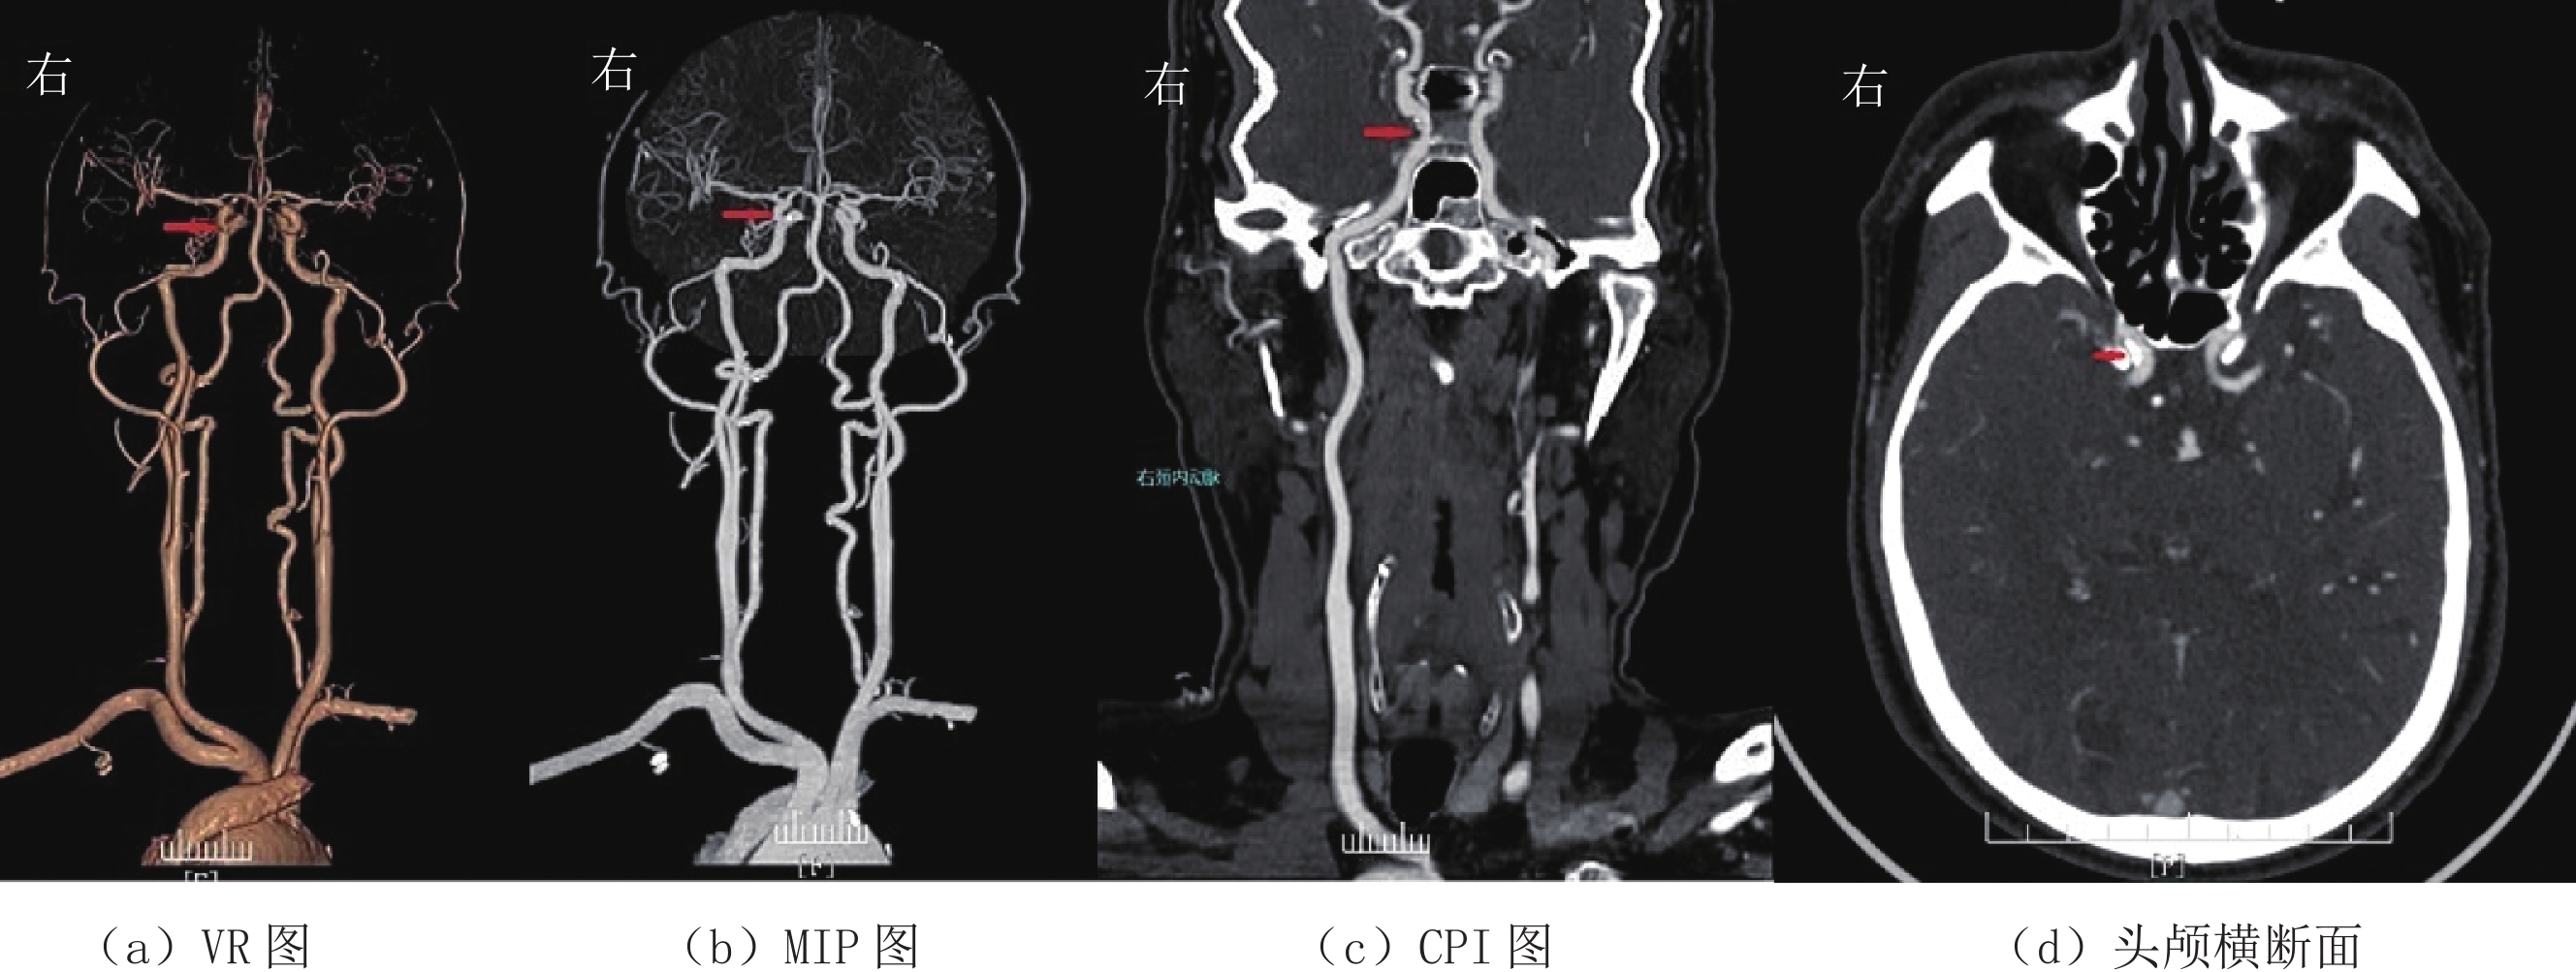

1.4.2 图像主观评分

采用双盲法由两位高年资主治医师对3组患者的横断面图像、VR、MIP以及CPI图像质量进行评分(图1~图3)。评分标准采用5分法[6],5分:图像质量好,血管与组织对比鲜明,细微解剖结构清晰,噪声小;4分:图像质量较好,血管与组织对比较好,解剖结构较清晰,噪声较小;3分:图像质量一般,血管解剖结构显示一般,噪声略大;2分:图像质量较差,血管解剖结构不清,噪声较重;1分:图像质量差,血管解剖结构不清,噪声极为严重。评分大于或等于3分视为满足诊断要求。

(1)众所周知,X线经过人体时会产生康普顿效应和光电效应;X线光子能量会随着管电压的下降而下降,当X线光子能量接近碘原子的K临界值(33 keV)时衰减值最大,这样导致所测得的CT值会随着管电压的下降而增高[13-15]。本研究结果显示:管电压从120 kV降到100 kV、80 kV时,大脑中动脉M1段血管的CT值分别为(334.21±69.42)HU、(385.00±85.53)HU、(502.50±110.17)HU,与学者的研究基本一致[10,16-18]。由于含碘血管腔的CT值是头颈部CTA图像质量的关键所在,也是观察血管病变和VR、MIP及CPI成像的基础。研究发现[16-18]血管腔内的CT值以350~550 HU时最佳,过低或过高都不利于血管细节的显示,会影响粥样斑块的显示和血管狭窄程度的判断。本研究大脑中动脉M1段血管CT值在管电压等于100 kV时最接近这个数值。同时,从本研究3组图像质量主观评分也可以看出管电压为100 kV时评分最高。两组数据都可以证明,管电压在100 kV时,图像质量最好。